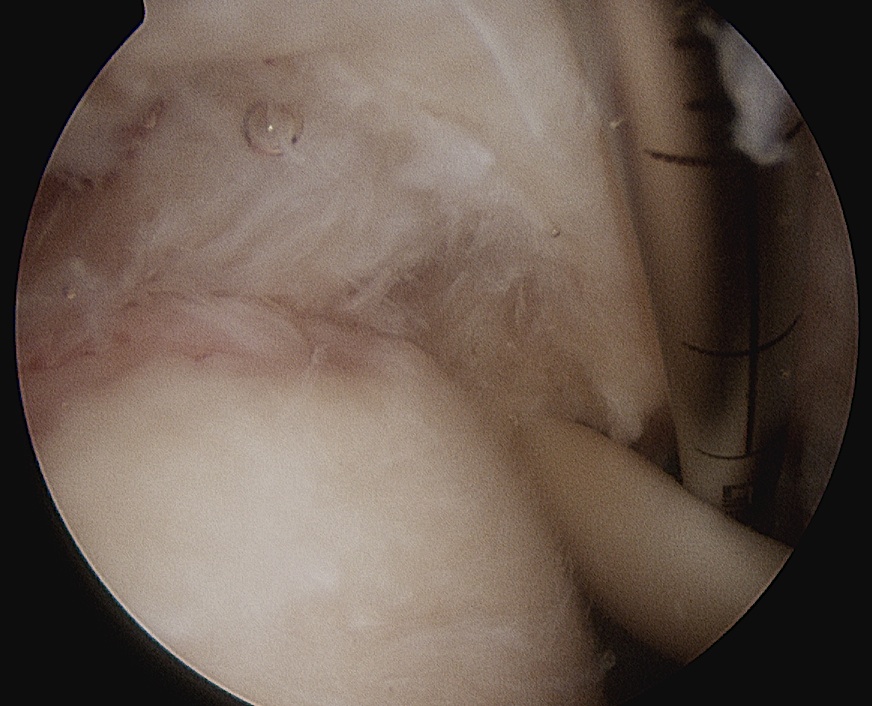

> 50% uncovering of footprint in glenohumeral joint